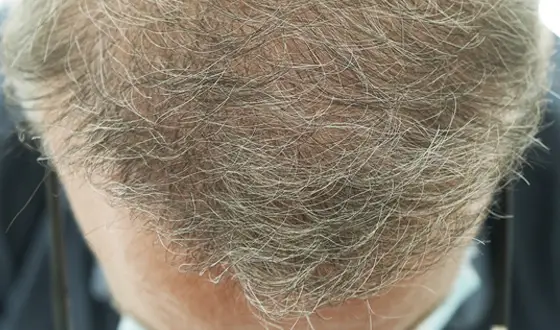

Plasma Rico em Plaquetas de 5 sessões

Após 6 meses

Após 6 meses

Plasma Rico em Plaquetas de 3 sessões